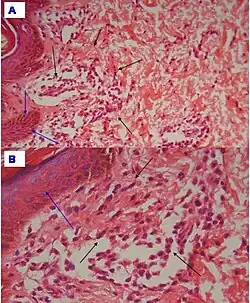

| Urticaria, lymphocyte predominant | Perivascular location. Mast cells are relatively sparse, potentially demonstrated with special stains, preferably tryptase stain. Extravasated erythrocytes are present in about 50% of the cases. No vasculitis.[14] | Dermal edema [solid arrows in (A,B)] and a sparse superficial predominantly perivascular and interstitial infiltrate of lymphocytes and eosinophils without signs of vasculitis (dashed arrow).[15]

| Urticaria, lymphocyte predominant | Perivascular location. Mast cells are relatively sparse, potentially demonstrated with special stains, preferably tryptase stain. Extravasated erythrocytes are present in about 50% of the cases. No vasculitis.[14] | Dermal edema (solid arrows) and a sparse superficial predominantly perivascular and interstitial infiltrate of lymphocytes and eosinophils (dashed arrow)

| Prevesicular stage of bullous pemphigoid | Image at right shows influx of inflammatory cells including eosinophils and neutrophils in the dermis (solid arrow) and blister cavity (dashed arrows), and deposition of fibrin (asterisks).[15] However, the diagnosis of bullous pemphigoid consist of at least 2 positive results out of 3 criteria:[19]